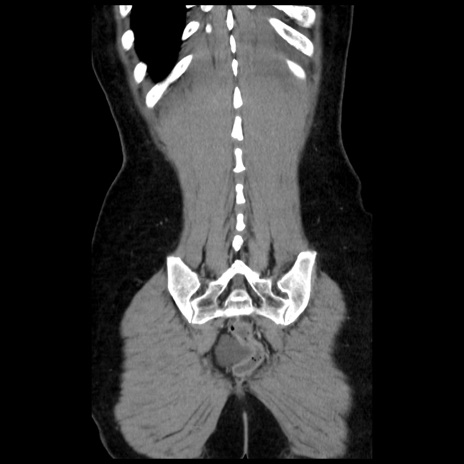

横断像

矢状断像